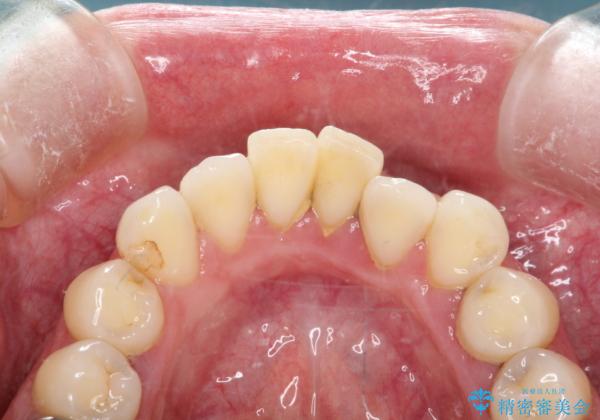

歯周病治療(歯石除去と歯磨き指導)

状態により、歯石除去の来院回数は変わります。また歯石除去をしても、ホームケアが安定していないと意味のない物となってしまう為、歯磨き指導はとても重要です。

患者様の協力がないと歯周病の進行は止められません。

歯石除去を進めていくと、歯肉が下がったり出血したり、知覚過敏が起きる事がありますので、不安にならないためにも、担当歯科衛生士の説明をしっかりと確認してくださいね。